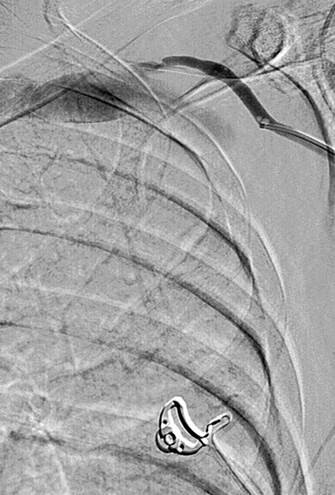

Thrombosed AV graft with stenosis at venous anastomosis.

AngioJet DVX catheter in AV graft.

Imaging post-AngioJet System activation in venous side of AV graft.

Imaging post-AngioJet System activation in arterial side of AV graft.